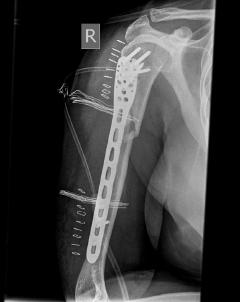

Περίπτωση 3ου ασθενούς

Με τα σύγχρονα μέσα που διαθέτουμε, όλα σχεδόν αυτά τα κατάγματα πρέπει να αντιμετωπίζονται χειρουργικώς. Υπάρχει πληθώρα υλικών οστεοσύνθεσης (πλάκες διαφόρων τύπων, ενδομυελικοί ήλοι, συστήματα εξωτερικής οστεοσύνθεσης) που είναι διαθέσιμα και επαφίεται στην εμπειρία του χειρουργού η επιλογή.

Οπως και άλλοι εξοικειωμένοι χειρουργοί διεθνώς, χρησιμοποιώ τεχνικές ελάχιστης παρέμβασης (Minimal Invasive Surgery), δηλαδή μικρές τομές, επειδή έτσι το χειρουργικό τραύμα είναι ελάχιστο, με αποτέλεσμα ταχύτερη επούλωση. Ταχύτερη πώρωση των καταγμάτων, ταχύτερη κινητοποίηση.

Τα εν λόγω κατάγματα είναι αρκετά συνηθισμένα και συχνά συμβαίνουν μετά από τροχαία ατυχήματα ή πτώση από ύψος. Παρατηρείται εξαιρετικά μεγάλη ποικιλία στη μορφή τους, κατα κανόνα όμως είναι σοβαρά και πολλές φορές ανοικτά – δηλ με τραύμα στο σημείο του κατάγματος – κάτι που αυξάνει τον κίνδυνο λοίμωξης και επιβαρύνει την πορεία της θεραπείας. Στα κατάγματα των άνω άκρων ενδέχεται να υπάρξει και τραυματισμός νεύρων, που χρειάζεται επίσης αντιμετώπιση.